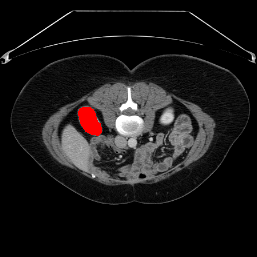

In order to assess the performance of the proposed method, we compare the performance of the proposed model with excellent models in recent years. Table 1 and Table 2 shows the comparison results of different models in setting1, while Table 3 and Table 4 shows the comparison results of different models in setting2 on the data set in recent years. PANet[25] is the most widely influential few-shot model in the field of few-shot image segmentation on natural images. SENet [18] is the first few-shot segmentation model proposed for medical images. SSL-ALPNet[19] introduced the milestone of using superpixel self-supervision to train few-shot medical image models. RPNet[29] is a supervised method with a recursive mask optimization module to iteratively optimize the segmentation mask, [27] adapt it into the same self-supervision learning framework and applies setting1 to it and denoted as SSL-RPNet; CRAPNet[27] is the latest SOTA model for 2023. Compared with CRAPNet, our method outperforms most of the state-of-the-art models and only slightly outperforms CRAPNet. Figures 3 and 4 show examples of the model’s segmentation predictions on different datasets, respectively; The first row is the support map, the second row is the label map, and the third row is the segmentation prediction of the model.